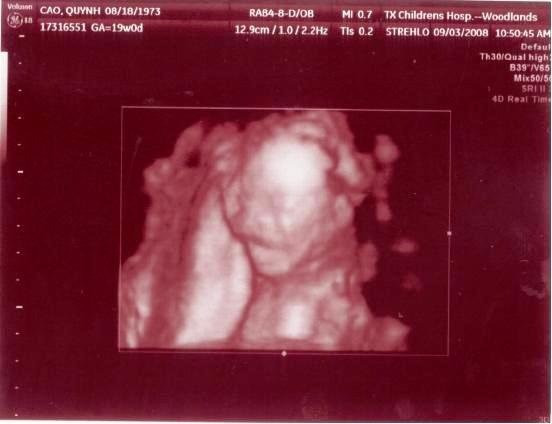

Ngày 11/28/1999 Ba Mẹ có nhau, lúc đó con ở đâu ha? Ngày 5/27/2008, con đây rồi!!! Mới được 2 tuần, là hạt nhân nhỏ xíu trong bụng Mẹ thôi Ngày 6/4/08, lần đầu tiên Ba Mẹ nghe tim con đập, 124 nhịp/phút. Mẹ sung sướng nhìn con. Còn Ba thì rơm rớm nước mắt, hihi!! Ngày 7/8/2008, con được 11 tuần rồi, bắt đầu có tay chân rồi đây... 1 tuần sau tay chân con đã dài ra rồi, lẹ ghê... ...biết nhào lộn vòng vòng nữa, mới nằm úp giờ nằm ngửa rồi. Ngày 9/3/2008, Mẹ chưa muốn biết con là trai hay gái vì muốn bất ngờ, nhưng rồi cuối cùng cũng không đợi được... ...hihi, cục cưng của Ba Mẹ là con trai. Con trai miệng bự giống Ba.  19 tuần là mắt mũi miệng đầy đủ hén. Từ khi biết có con, Mẹ nhờ Ba chụp hình hai mẹ con mình. Cái này là lúc con được 2 tháng trong bụng Mẹ.. ...24 tuần, con bắt đầu cựa quậy lung tung mỗi ngày... ...36 tuần, có lúc Ba Mẹ tưởng đã mất con nhưng con vẫn lớn giỏi ngoan... ..39 tuần, con nặng quá rồi nhưng Mẹ vẫn muốn con ở trong đó thêm chút nữa cho lớn lớn... Ba thì nôn gặp con quá, ngày nào Ba cũng nói chuyện với con.  Bụng Ba cũng bự rồi nè! Ngày 1/20/2009, con 39 tuần, bác sĩ muốn con ra sớm cho an toàn.  Ba Mẹ hồi hộp đợi tới lúc gặp con... Sau gần 8 tiếng chờ đợi thì con ra đời!! Con mở mắt nhìn Mẹ như là biết rồi đó.  Thương con ghê nơi! 1 tuần tuổi thì rụng rún.  2 tuần tuổi thì chụp hình lần đầu với Mẹ, nhỏ xíu xiu xiu... 7 tháng (8/2009) con bò lung tung, chụp hình mà không yên... 14 tháng (4/2010) con chỉ muốn chạy chơi thôi, Ba chụp lẹ lẹ nghe. Ngày 2/19/2010 Ba Mẹ làm lễ cưới ở nhà thờ.  Lần này thì có con rồi.  Có con Ba Mẹ có tất cả...